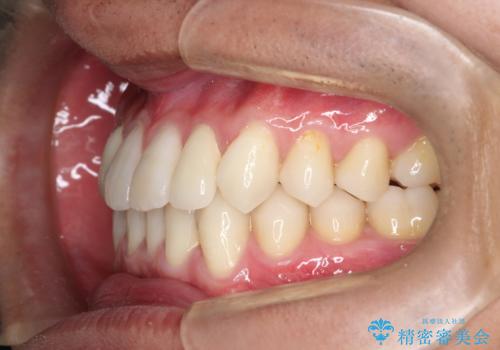

- 前歯のがたつきが気になるとのことで来院されました。

骨格的なところと、上下の歯の大きさのことを考慮して、下の前歯を1本抜歯し、インビザラインにて矯正治療することとなりました。

上の前から2番目の歯がもともと小さかったため、最後にかぶせ物を装着することで、自然な仕上がりにできました。